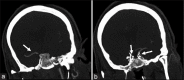

Solitaire FR device is a Food and Drug Administration-approved device for mechanical thrombectomy. It has been tested in various clinical trials for its safety and efficacy. We report a case of inadvertent detachment of the Solitaire FR device at stent-stent wire interface while performing mechanical thrombectomy. We review a rare phenomenon of retained Solitaire FR stent retriever in situ and discuss technique of avoidance and its management.